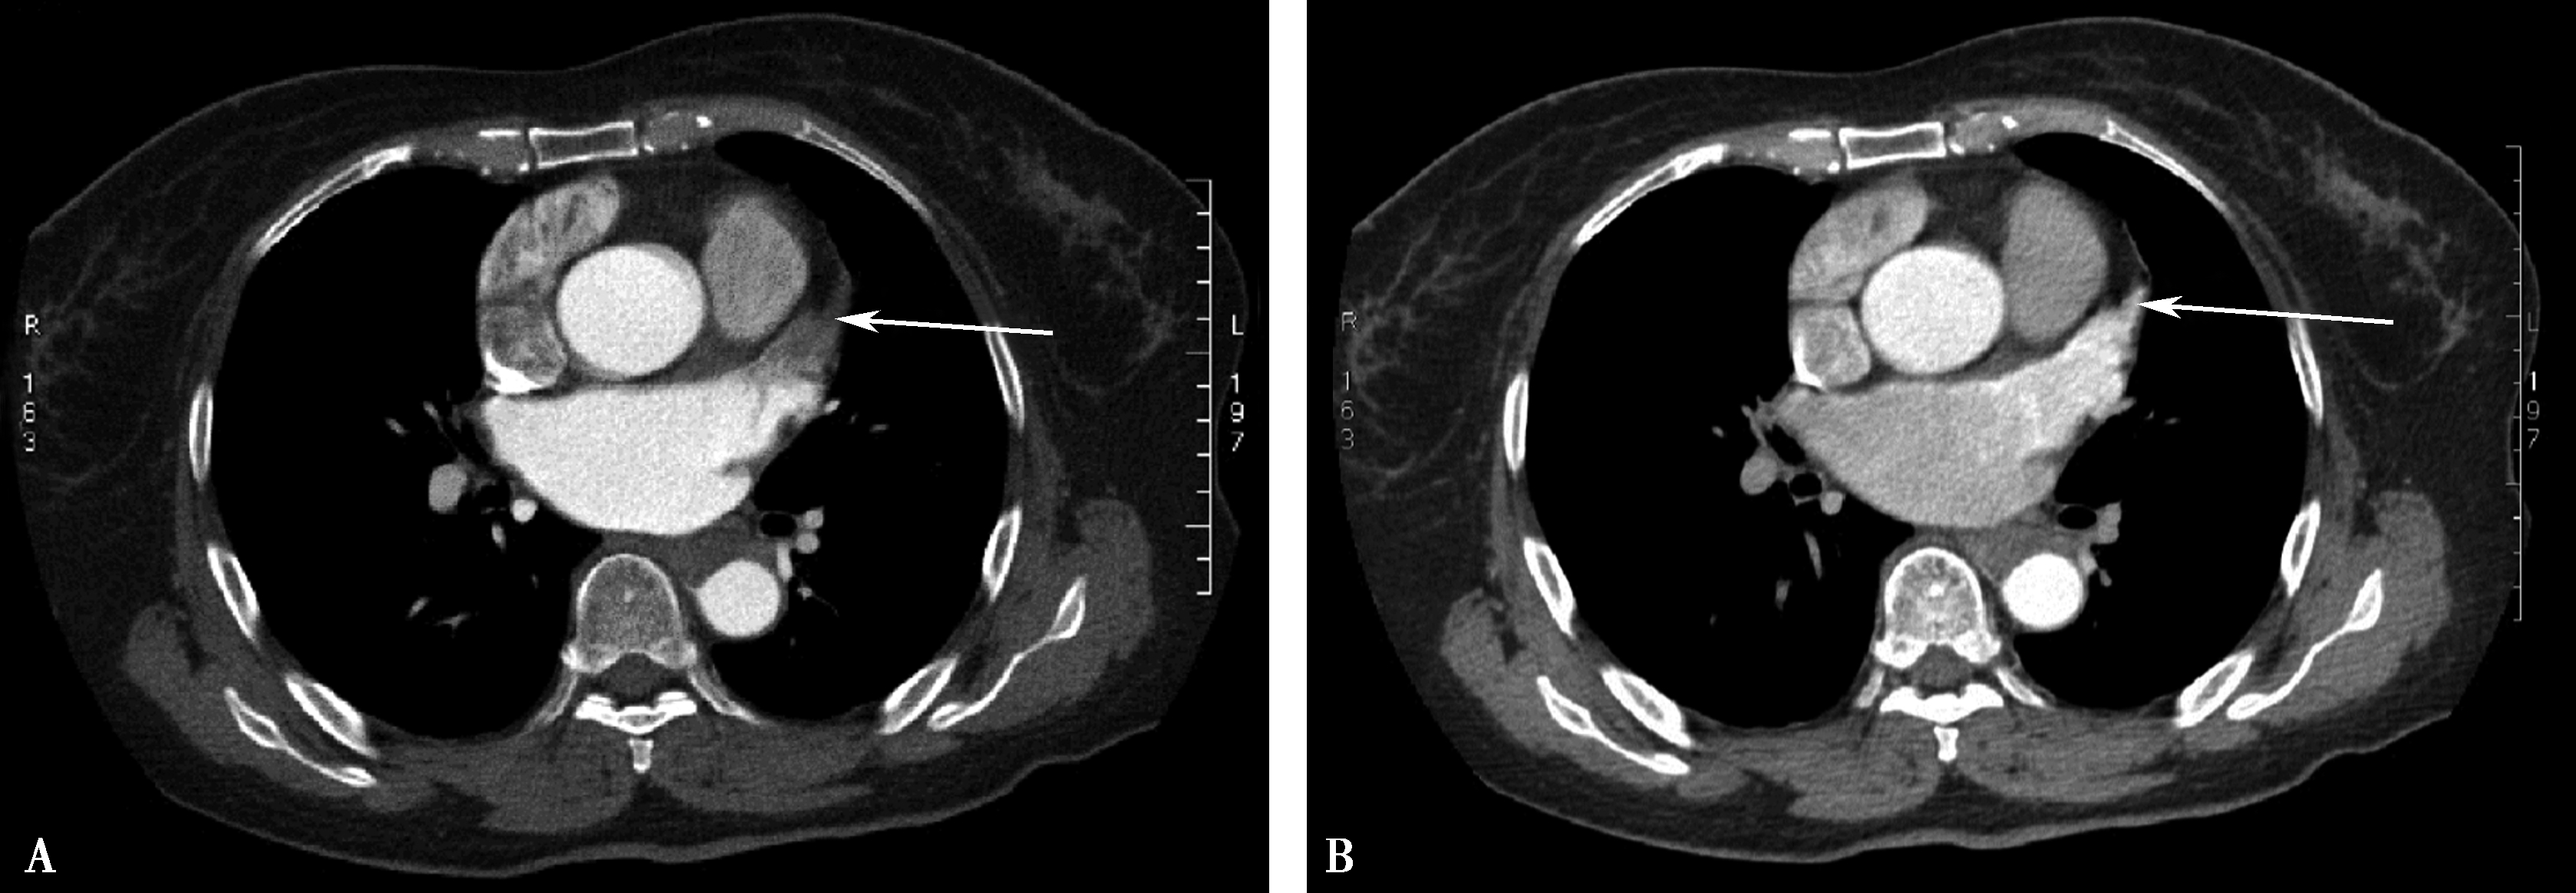

图8-1-5 CTPA两期扫描应用:患者,男,37岁,二尖瓣狭窄,肺循环高压,怀疑肺栓塞。第一期右肺下叶基底段对比剂充盈不充分(ABC↑);第二期充盈充分(DEF↑),排除肺栓塞诊断

(二)双期扫描法(图8-1-5)

1.患者仰卧位,足先进,仰卧于检查床上。对检查范围以外的部位用铅衣、铅帽遮盖做好防护。

2.对比剂 对比剂浓度370mgI/ml,采用单筒高压注射器团注,流率为4.0~5.0ml/s,对比剂总量为70~90ml,如加做下肢静脉造影,可增加对比剂剂量为120~150ml。

3.扫描的范围 从肺尖到膈肌。

4.扫描采用的对比剂跟踪技术,监测层面设定在上腔静脉入右心房的层面,ROI定为上腔静脉,触发阈值定义为80~100HU。

5.当ROI的CT值达到阈值时启动增强扫描程序。实行双期扫描,第一期为肺动脉期,从肺尖扫描至膈肌,第二期为主动脉期,由膈肌扫描至肺尖,双期扫描范围一致。双期扫描的意义在于:①充分保证了对比剂团注时间与肺动脉CT数据采集时间的吻合;②肺动脉高压或/和右心功能不全循环时延长者,是一弥补措施;③多期观察可以辨别对比剂充盈不均造成的假象;④有利于对肺灌注的评价;⑤主动脉期可以兼顾观察左心系统的病变。